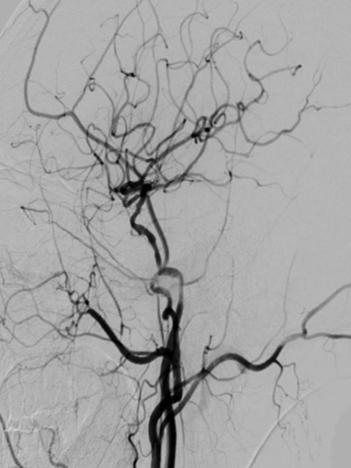

导丝怎么扩【载药时代 球扩天下】NOVA DES®颅内药物洗脱支架在颈内动脉颅内段重度狭窄的应用二例!_https://www.jmylbn.com_新闻资讯_第27张

DSA

重要影像结论:左侧颈内动脉C4段重度狭窄。

治疗中影像

导引导管到位,导丝通过病变,球囊通过病变。

导丝怎么扩【载药时代 球扩天下】NOVA DES®颅内药物洗脱支架在颈内动脉颅内段重度狭窄的应用二例!_https://www.jmylbn.com_新闻资讯_第28张

球囊扩张过程。

导丝怎么扩【载药时代 球扩天下】NOVA DES®颅内药物洗脱支架在颈内动脉颅内段重度狭窄的应用二例!_https://www.jmylbn.com_新闻资讯_第29张

扩张后造影。

导丝怎么扩【载药时代 球扩天下】NOVA DES®颅内药物洗脱支架在颈内动脉颅内段重度狭窄的应用二例!_https://www.jmylbn.com_新闻资讯_第30张

支架通过病变。

导丝怎么扩【载药时代 球扩天下】NOVA DES®颅内药物洗脱支架在颈内动脉颅内段重度狭窄的应用二例!_https://www.jmylbn.com_新闻资讯_第31张

支架释放。

导丝怎么扩【载药时代 球扩天下】NOVA DES®颅内药物洗脱支架在颈内动脉颅内段重度狭窄的应用二例!_https://www.jmylbn.com_新闻资讯_第32张

术后影像及检查

术后造影。

导丝怎么扩【载药时代 球扩天下】NOVA DES®颅内药物洗脱支架在颈内动脉颅内段重度狭窄的应用二例!_https://www.jmylbn.com_新闻资讯_第33张